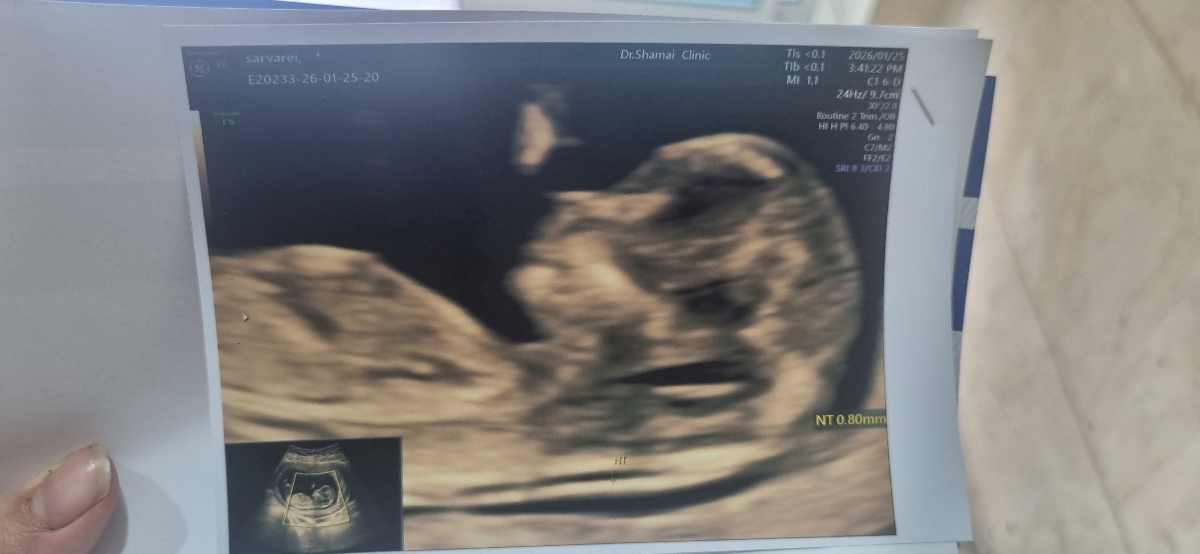

دل انگیز .

ای خدا گوگولی

خداحفظش کنه .به احتمال ۹۹درصد میگم دختره😍😍😍😍😍

عکس سونوت خیلی شبیه عکس سونوی دخترام هست

گردی سر و پیشونی

گردی سرش

سرش عزیزم

پیشونی تاپشت گردن

گرد هست

چه عکس خوبی دکتر با سلیقه بوده همیشه همینجا برو🤣

بنظر منم دختره کله اش گرد و ظریف به نظر میرسه